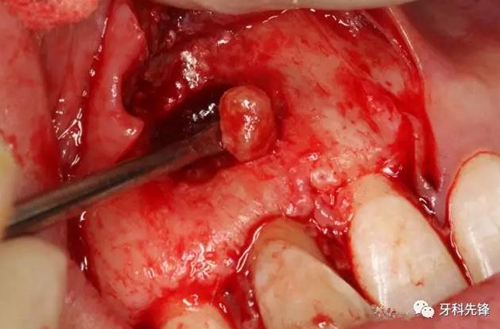

圖11.取出囊腔內(nèi)的致密團(tuán)塊。

圖12. 取出沒有完全鈣化形成的牙齒。

圖13.摘除囊壁。

圖14.摘除后的囊腫情況,并用超聲骨刀清理根尖區(qū)后,可清晰看到12牙根未發(fā)育,根管粗大開放。